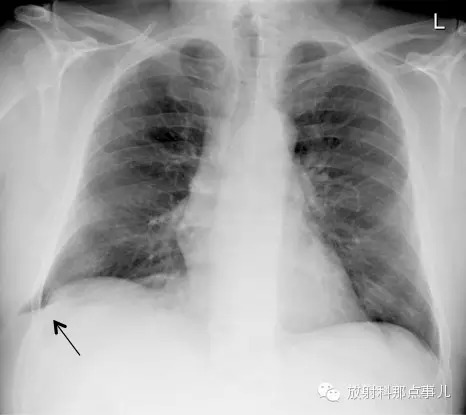

【基本病史】患者咳嗽后出现胸痛症状。

胸部 X 线片显示左肺的基底部肺实质影延伸到胸廓左肋的外侧。胸部 CT 检查结果证明上述结论,左肺实质通过左下肋间外侧疝出,同时左侧胸腔伴有中等量胸腔积液。

另一例肺疝胸部X光片